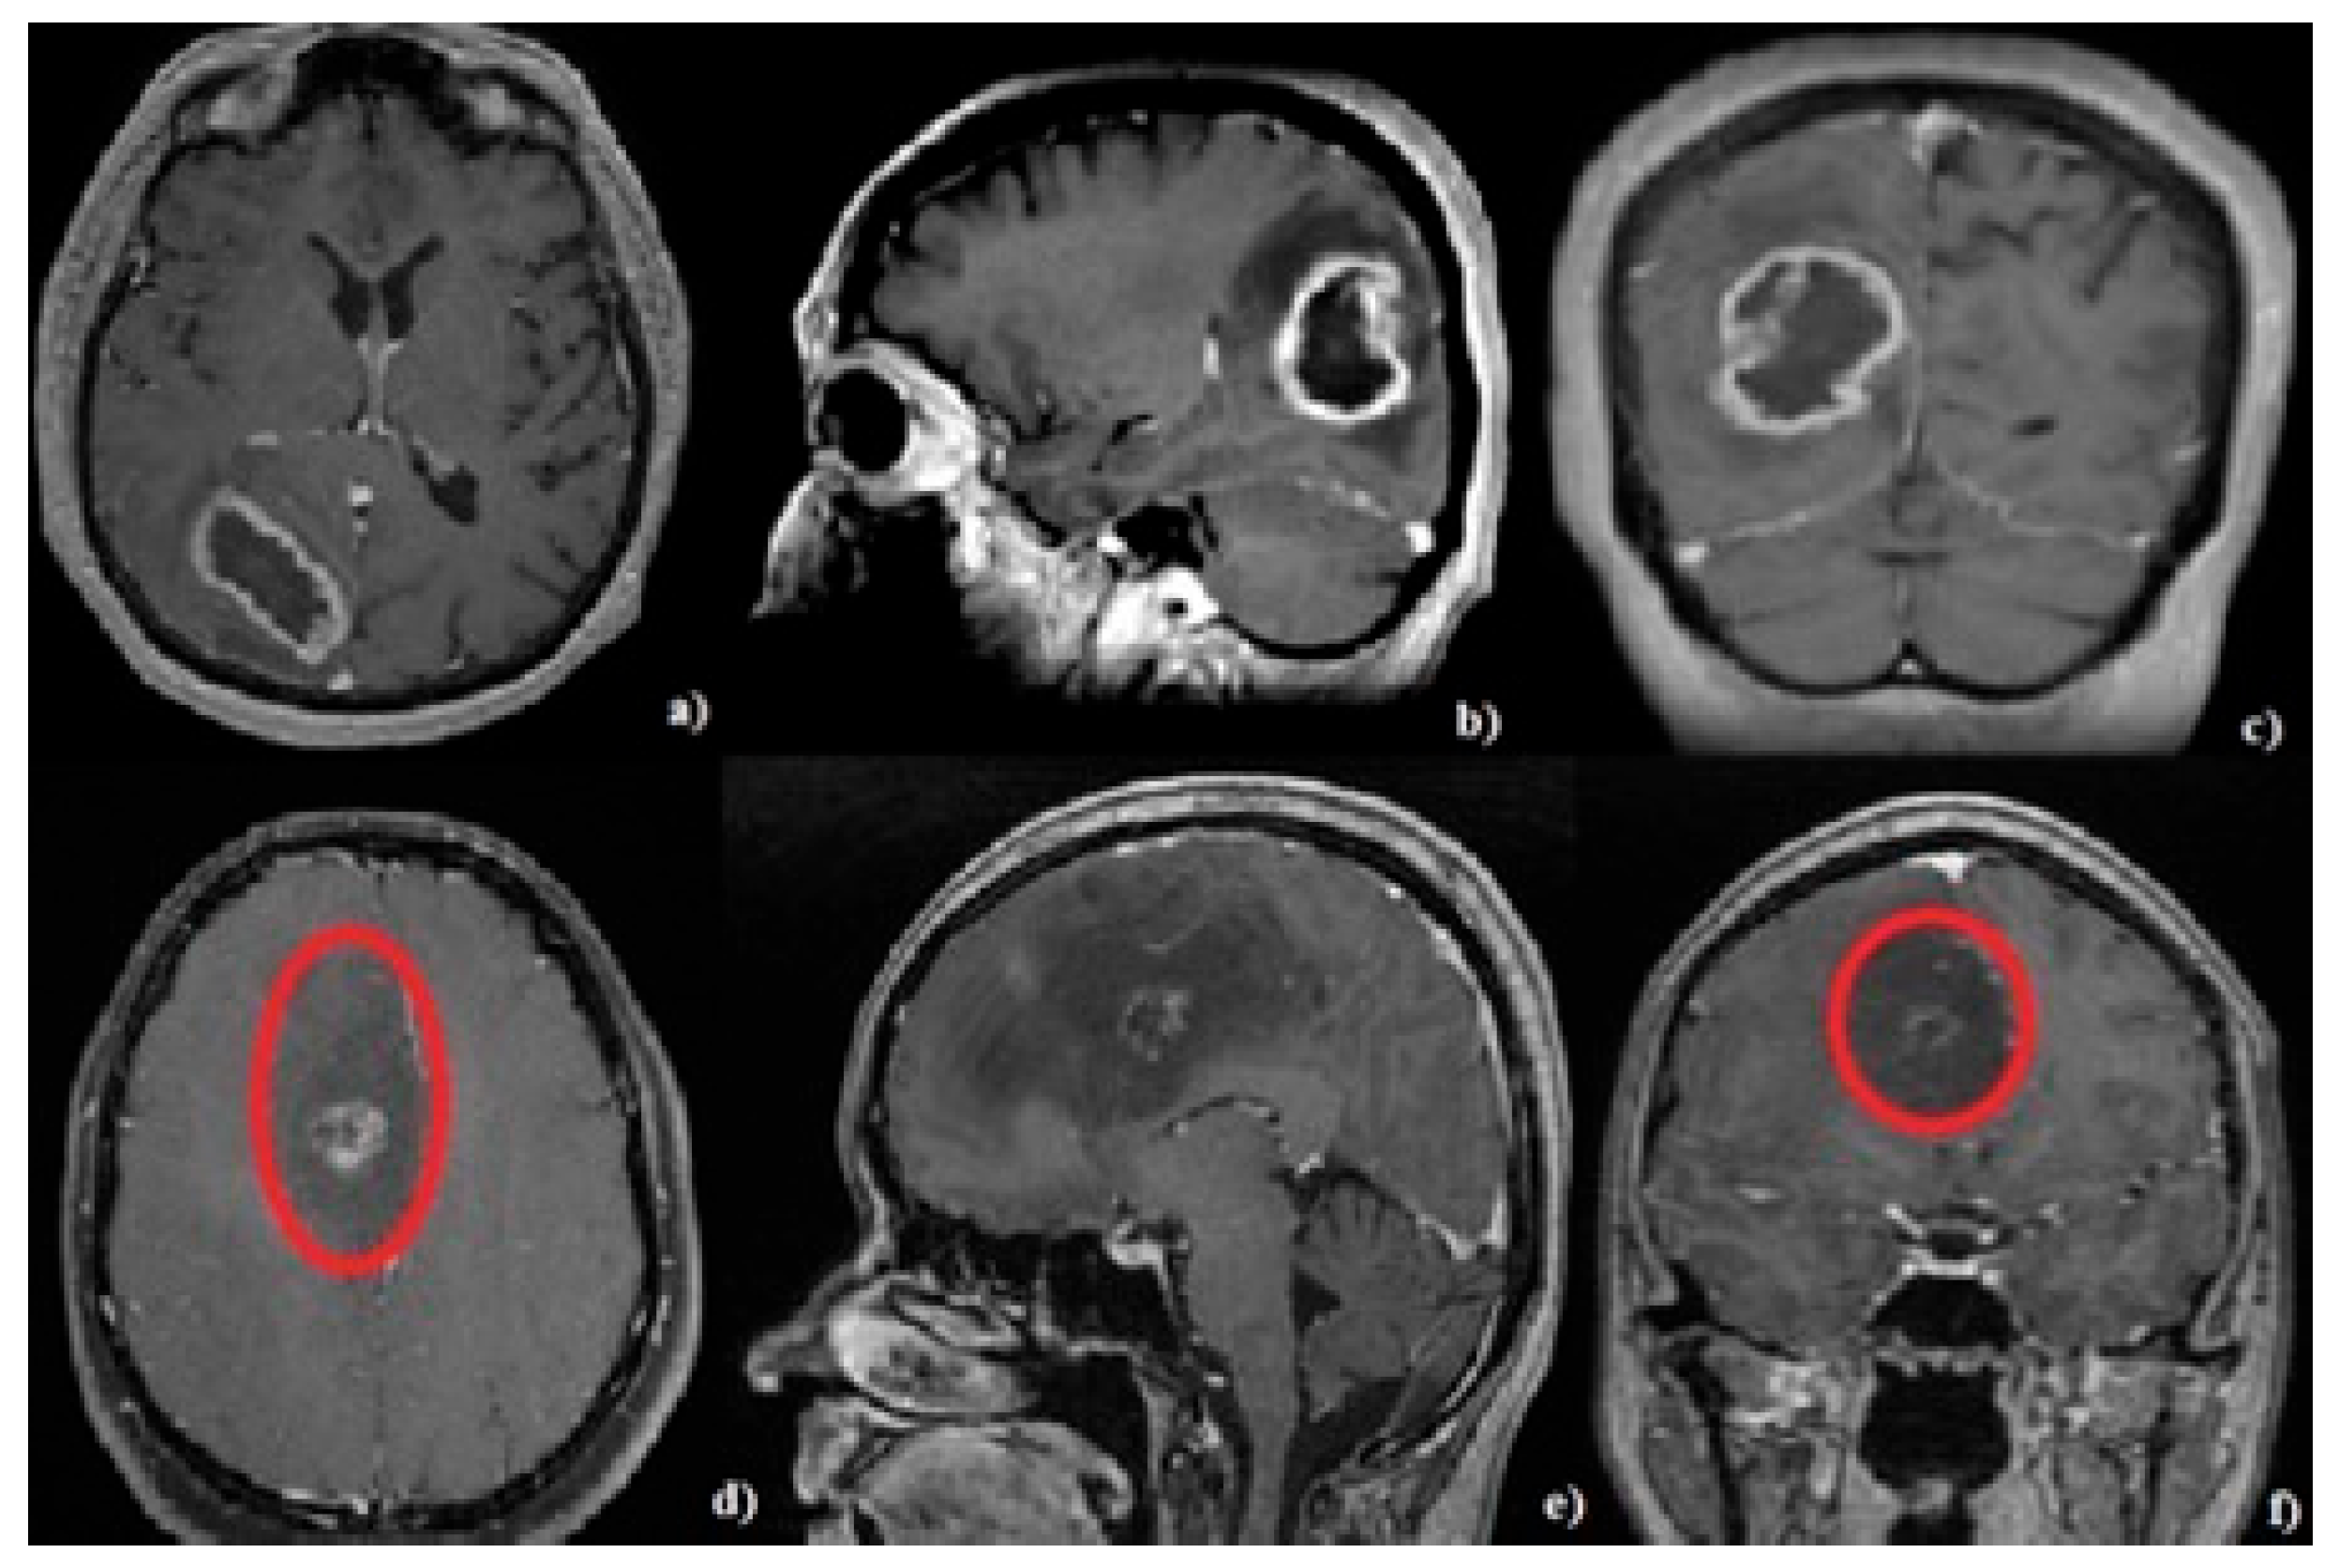

2.5. Neuroimaging Evaluation

3.3. Tumor Characteristics

3.4. Histopathological Features